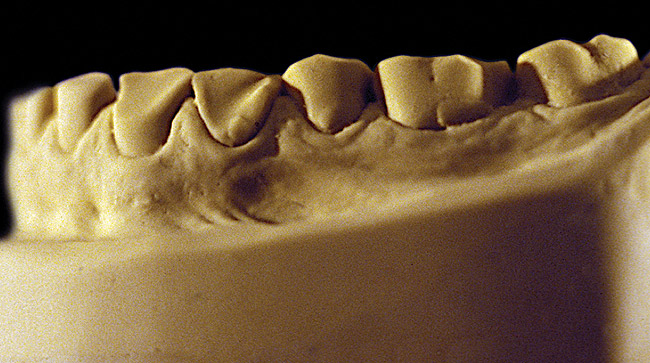

Figure 9  Moderate NCLTS from toothpaste, right facial view.

Figure 9

Figure 10  Moderate NCLTS from toothpaste, left facial view.

Figure 10

Figure 7 and Figure 8 are examples of NCLTS resulting from toothpaste. Upon examination, one could see that the overall anatomical detail of the teeth was faded with a sandblasted appearance. A closer view of the facial surfaces (Figure 9 and Figure 10) illustrates this to a greater degree and one can observe that the normal intricate facial anatomy was completely missing. It is interesting to note there was no cervical recession of the gingiva, even though every surface of every tooth had been abraded. This is due to the fact that this patient had always used a soft, round-ended filament toothbrush.21-22 This patient's sole desire regarding her oral hygiene was to get her teeth whiter.